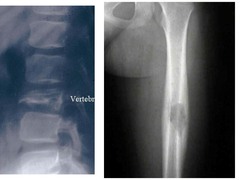

Paget disease

Front